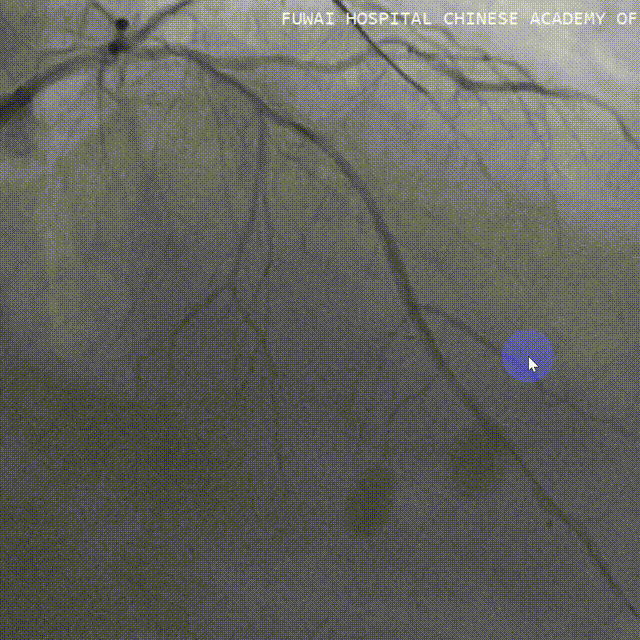

右头位造影提示LM、LAD重度狭窄伴钙化